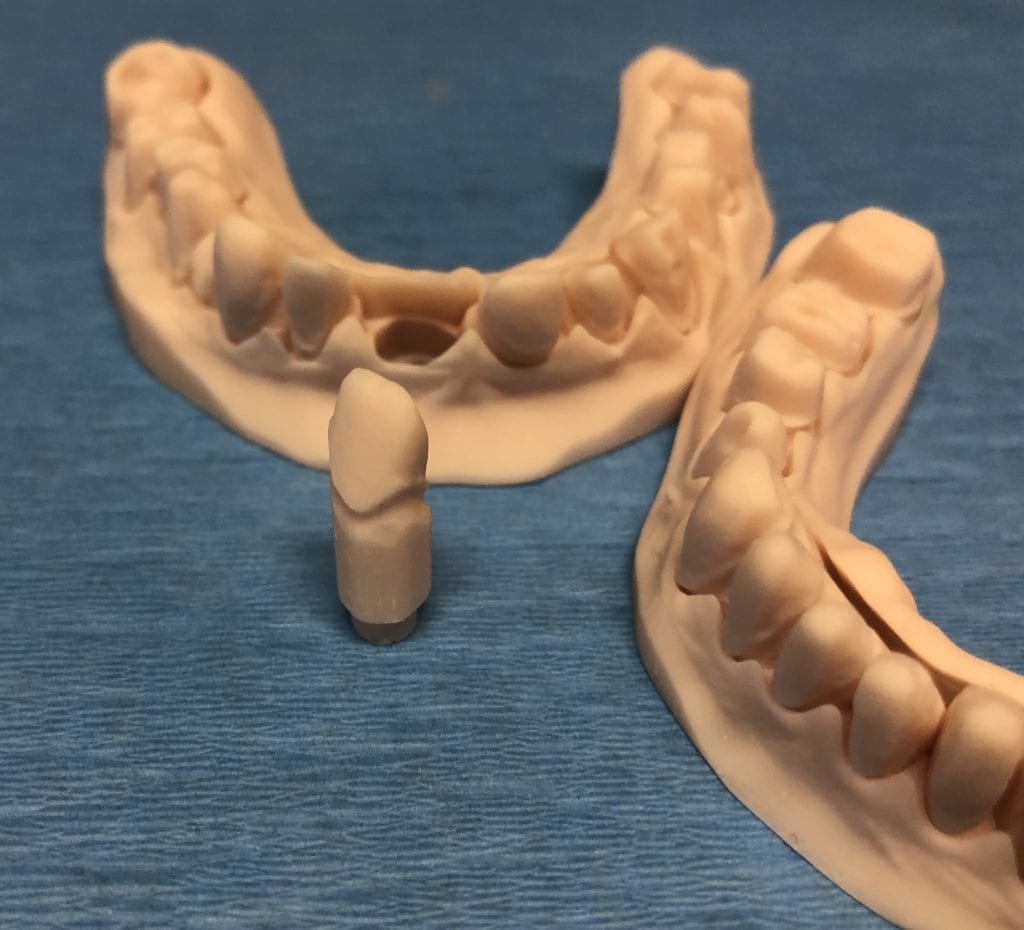

The case was designed by CADENT BESSA, and the models were printed by Burbank Dental Lab with Carbon Printers. There restorations were milled and cut back and layered by Burbank Dental Lab

IMAGES OF PRINTED MODELS